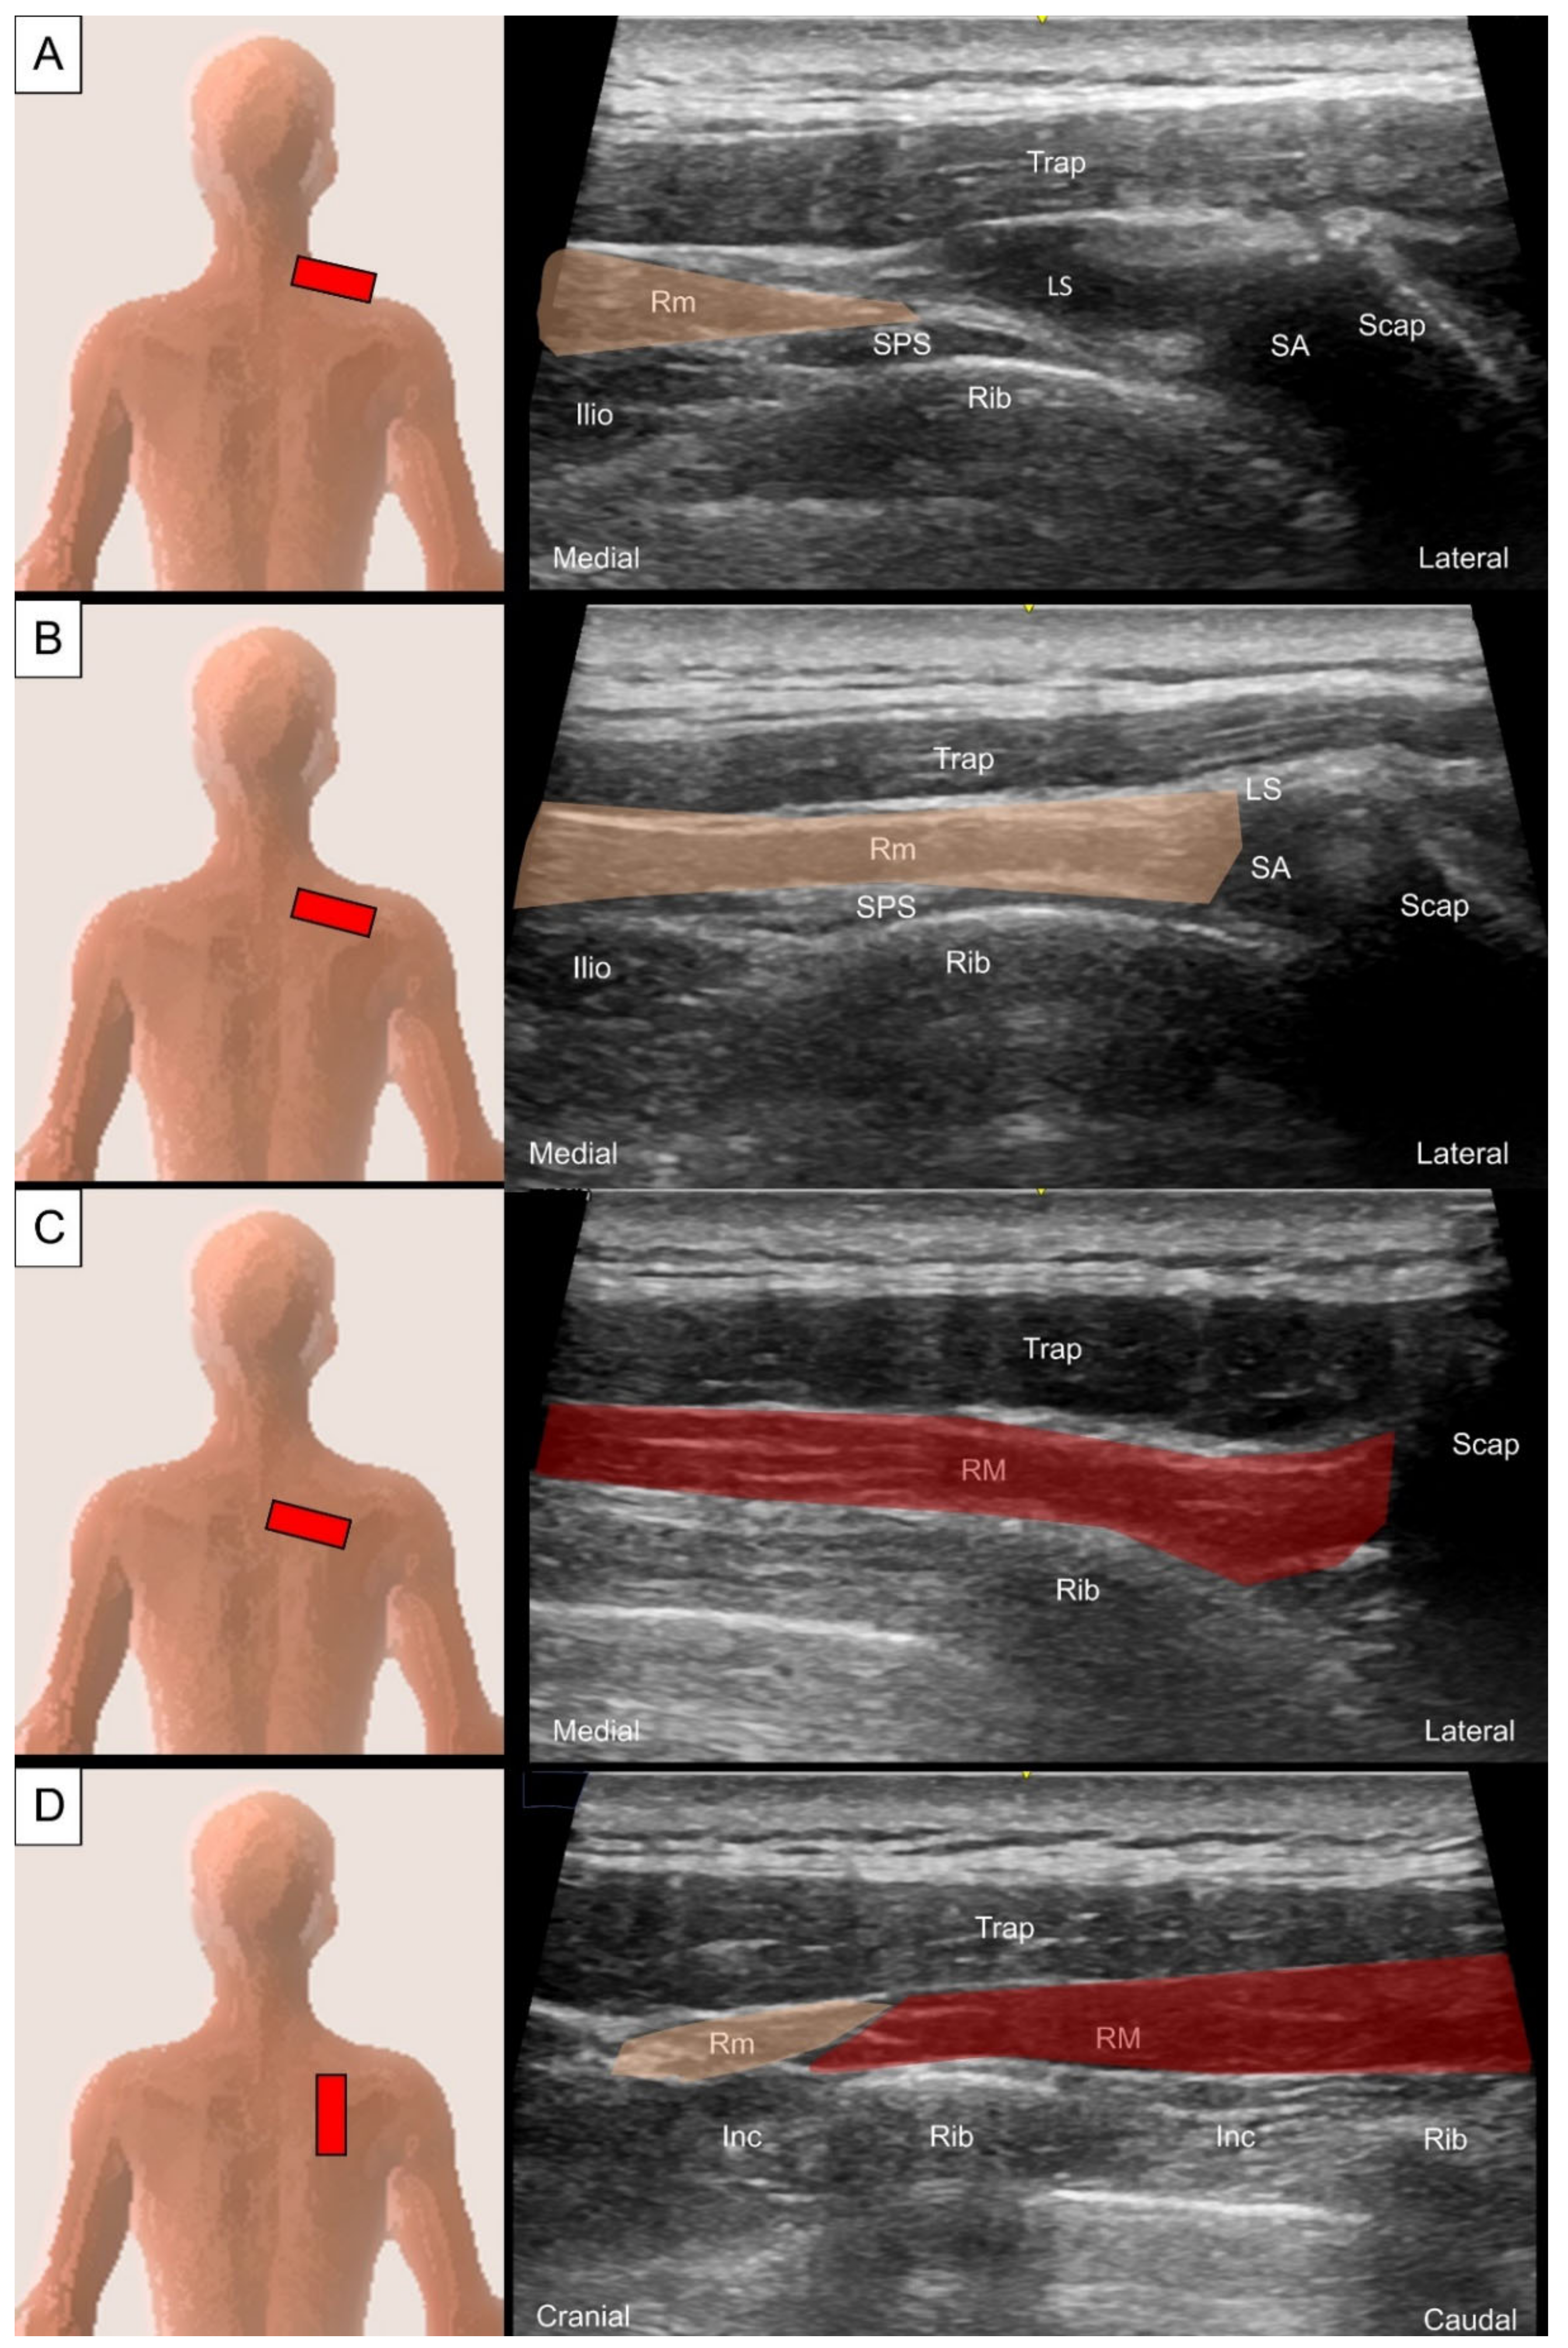

2.2. Rhomboids

2.2.2. Sonographic Scanning

2.2.3. Clinical Relevance